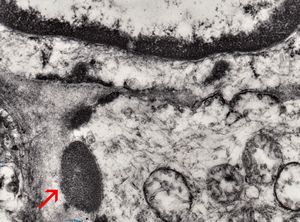

F,49y. | purulent meningitis- meningococcal v.s.

F,49y. | purulent meningitis- meningococcal v.s.

F,49y. | purulent meningitis- meningococcal v.s.